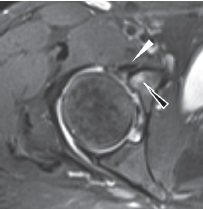

Как уже было сказано ранее, повреждение суставной губы чаще всего локализуется в передне-верхнем квадранте, что связано с наибольшей функциональной нагрузкой на этот отдел и повторяющейся травматизацией вследствие ФАИ. Нормальная суставная губа вертлужной впадины выглядит как треугольник слабого МР-сигнала с гладкими краями, плавно переходящий в хрящ вертлужной впадины или отделенный от него сублабральной бороздой. Распространенной ошибкой при оценке МРТ является определение сублабральных углублений как повреждений. Это нормальные варианты, которые, как правило, не распространяются на всю толщину суставной губы, доходят проекционно до уровня субхондральной кости и чаще наблюдаются в передне-нижней или задне-нижней части вертлужной впадины [78]. Расположение сублабральной борозды в передне-верхнем отделе стоит внимательно дифференцировать с повреждениями, которые встречаются в этой области чаще [79] (рис. 7).

Рис. 7. Сублабральная борозда:

а — МРТ-картина сублабральной борозды;

b — вид сублабральной борозды во время артроскопии

Fig. 7. Sublabral sulcus:

а — MRI picture of sublabral sulcus;

b — sublabral sulcus arthroscopy view

Чаще всего встречаются продольные повреждения хондро-лабрального перехода с отслойкой или без отслойки суставного хряща от подлежащей субхондральной кости или горизонтальное расслоение суставной губы, нередко ведущее к образованию интралабральных или паралабральных кист, в том числе и в зоне прилегания сухожилия подвздошно-поясничной мышцы с распространением кисты по ходу сухожилия [80, 81].